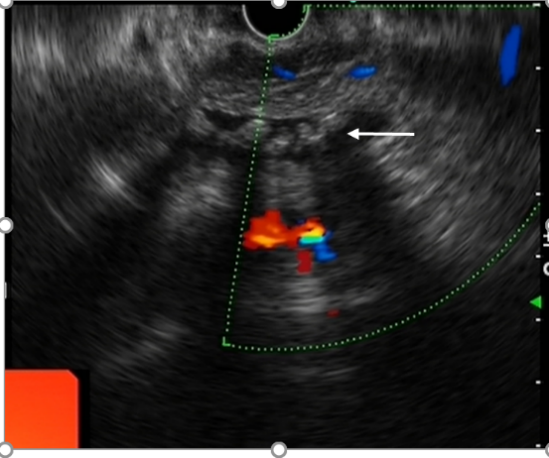

5、肝脏、胆管及十二指肠壶腹部病变的诊断对于存在梗阻性黄疸的患者,沿胆管走行扫查可以精确定位梗阻位置,通过观察梗阻部位病变的形态及回声特点,判断病因是结石、肿瘤或者其他疾病,并明确周围组织器官受累情况。

胆总管下段结石